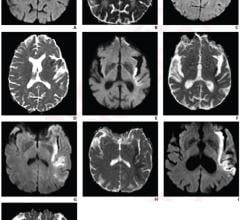

Aug. 12, 2025 – Medical imaging methods such as ultrasound and MRI are often affected by background noise, which can ...